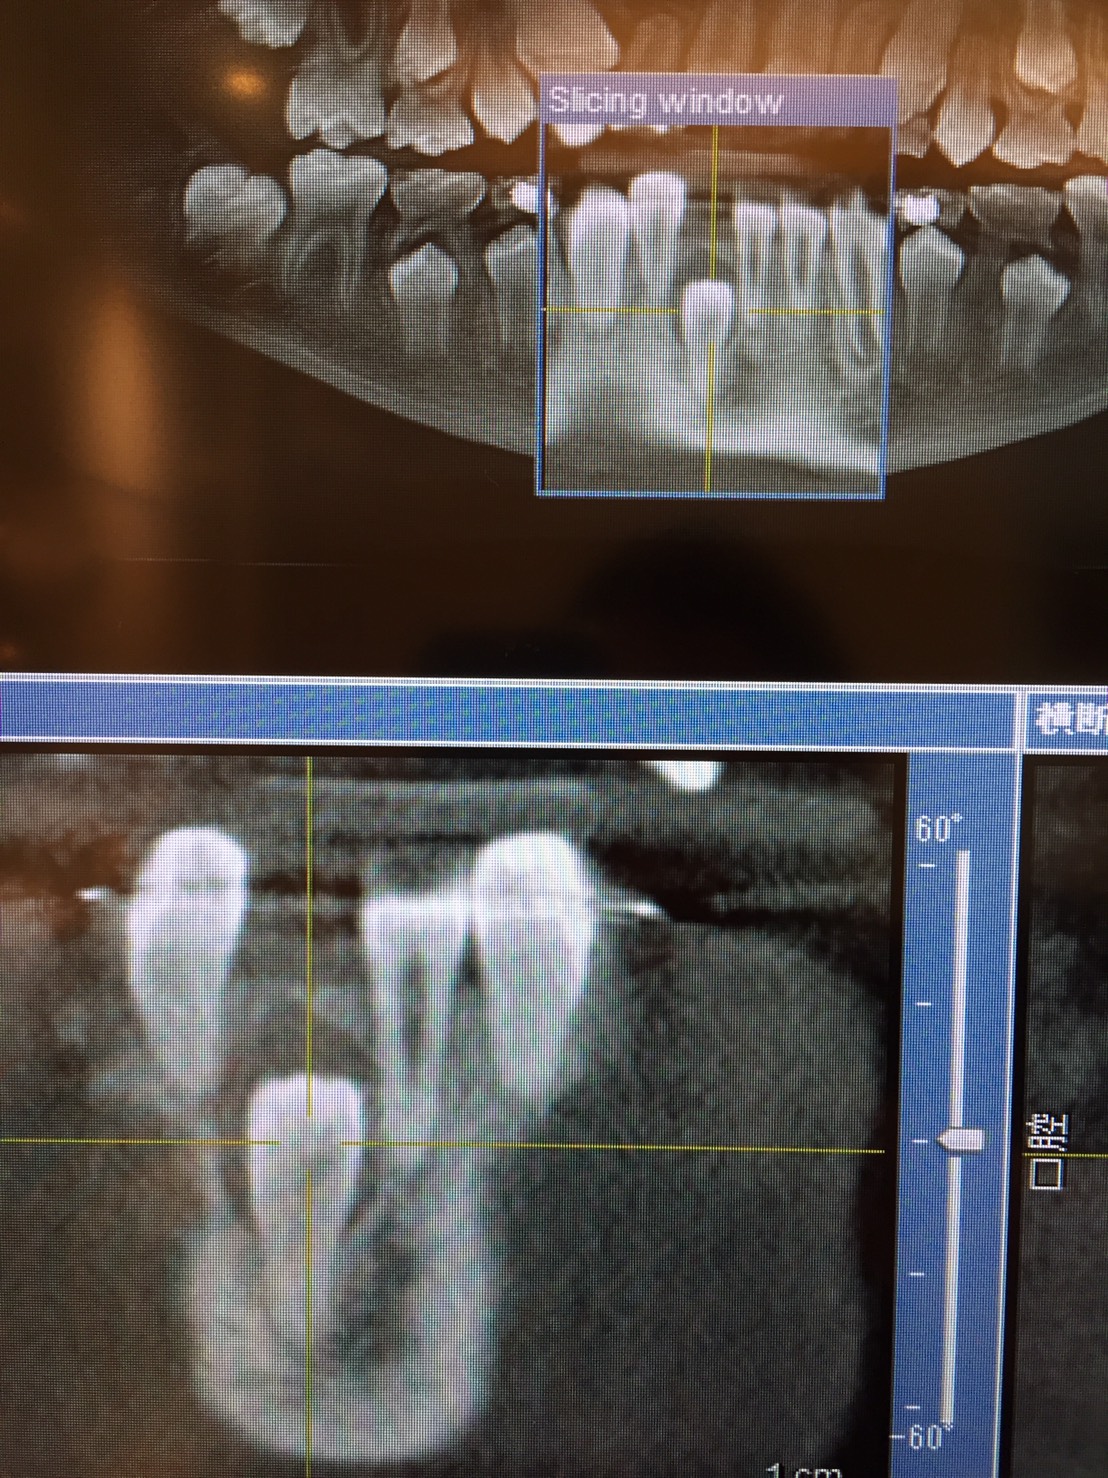

レントゲンを撮影してこれから生えるべき永久歯が存在するのか、存在するのであればどのくらいの深さ、場所にあるのかを見ます。

歯があるのに生えてこない場合には歯の生えてくる隙間があるのかをチェックして必要があれば矯正治療で隙間を広げてあげることもあります。隙間を広げても出てこなあい場合にはCTを撮影して、永久歯の周りに病変がないかや三次元的な位置を調べます。